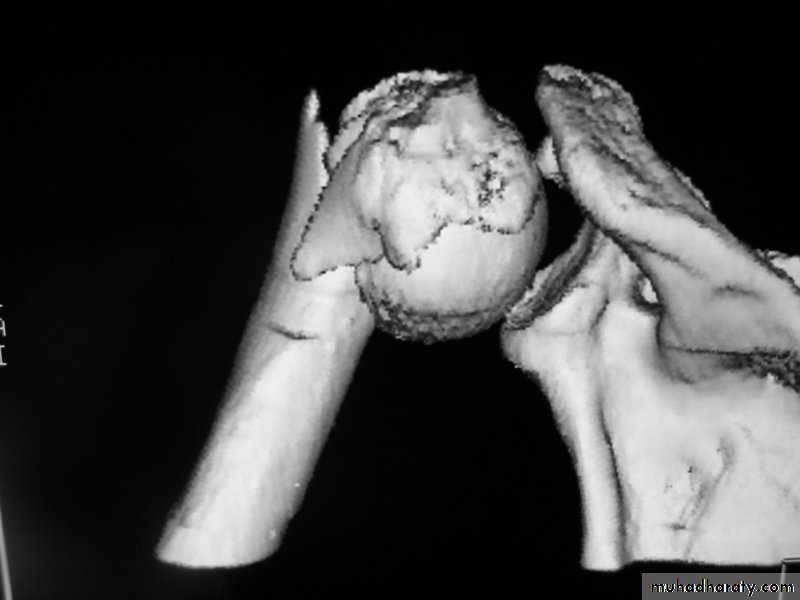

C-T scan

Indications:

Segmental bone necrosis.

Depressed fracture in cancellous bone.

Small radiolucent lesion; eg oseoid osteoma.

Bone and soft tissue tumors.

Complex fractures of spine, pelvis, tarsal and carpal bones.

3-D reconstructed images.

Disadvantage: high radiation exposure.

3-D C-T in fracture pelvic ilium